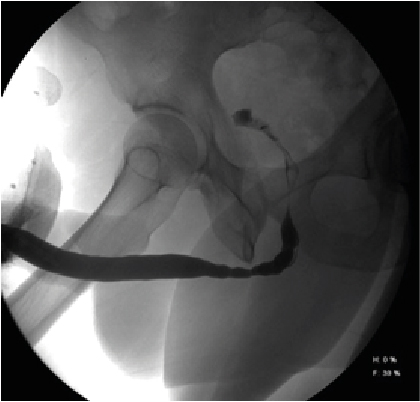

Retrograde urethrography is a very dynamic study, which must be taken into account when acquiring images, especially when sending still images, a common error is the leakage of contrast towards the skin (Figure 1) avoiding using a Foley catheter at the level of distal urethra to retain the contrast, however it can condition trauma [1]. Another common error is the ignorance of ideal projections for evaluation of the urethra (Figure 2), for example the Lauenstein projection, which is more useful for evaluating the hip. The imaging with a lack of contrast between the structures (Figure 3), which can be modified during and after the acquisition. It should be noted that on some occasions, in case of doubt, images will be taken from two different x-ray directions.

Figure 2:  AP Projections with Oblique Taking of the Penis, Avoiding Adequate Visualization of the Urethral Route